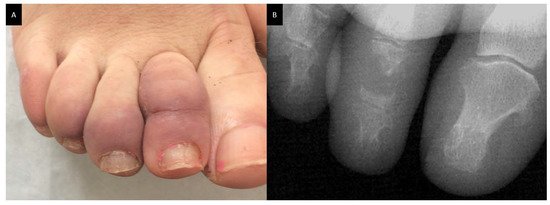

Bone sarcoidosis is observed in 0.5% to 30% of patients depending on the sensitivity of imaging procedures and is frequently associated with lupus pernio, uveitis and a chronic multisystemic course of the disease [60]. On the other hand, Sparks et al. reported only 20 cases (1.5%) of osseous involvement detected in 2013 patients with sarcoidosis identified between 1994 and 2013 at Brigham and Women’s Hospital in Boston, Massachusetts [66]. Bone lesions are asymptomatic in half cases. They are commonly located in the phalanges of the hands and feet and are usually bilateral. Dactylitis typically involves the bones and soft tissue with slight swelling, tenderness and limitations of the movement (Figure 4A). The skull, as well as long bones, ribs, pelvis and axial skeleton may also be affected. Radiographic investigations may revelate sclerotic (typically in the spine) and/or osteolytic lesions, cystic and punched out lesions and cortical abnormalities (Figure 4B).

Figure 4. Dactylitis in a sarcoidosis patient; (A): skin on clinical examination; (B): X-ray on the same patient with punched out lesion of the second phalanx.